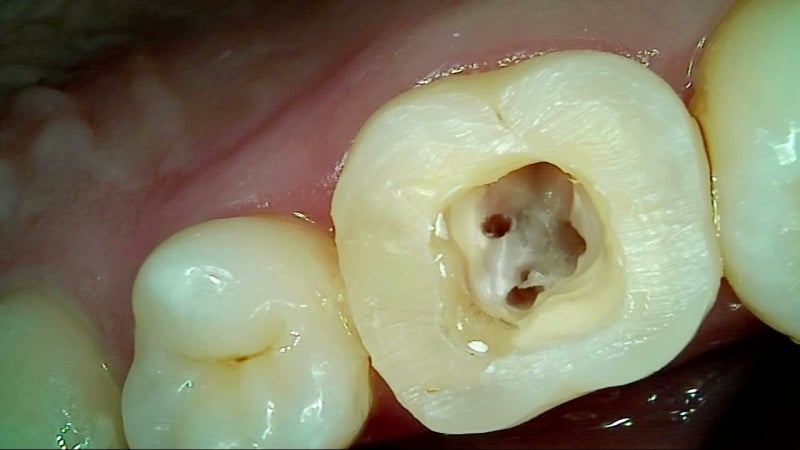

신경치료 후 치아는 내부 구조가 약해져 쉽게 깨질 수 있습니다. 크라운은 이를 보호하고, 씹는 기능과 심미성을 복원해주는 중요한 치료 단계로, 선택이 아닌 필수입니다.

크라운은 손상된 치아 위를 씌우는 인공 보철물로, 치아를 외부 충격에서 보호하고 정상 기능과 자연 외형을 회복시켜 줍니다. 어금니는 내구성, 앞니는 심미성을 고려해 재료를 선택하는 것이 핵심입니다.

1. 치과 신경치료란?신경치료(근관치료)는 치아 내부의 손상된 신경(치수)을 제거하고, 그 공간을 소독한 후 밀봉하여 감염을 막는 치료입니다. 충치가 깊어져 신경까지 침범하거나 외상, 감염